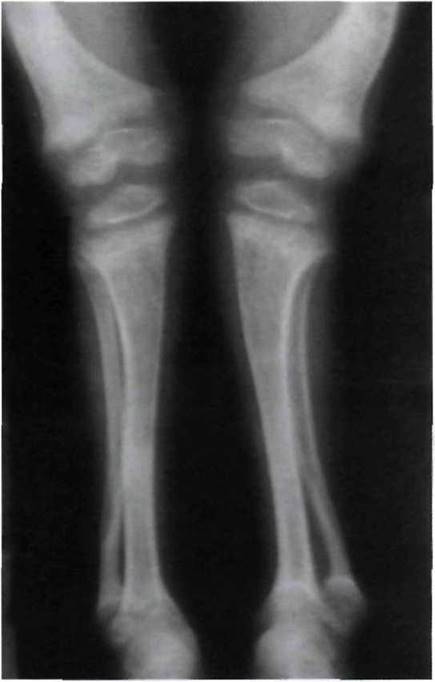

Рис. 11-2. Рентгенологические проявления рахита в период разгара.